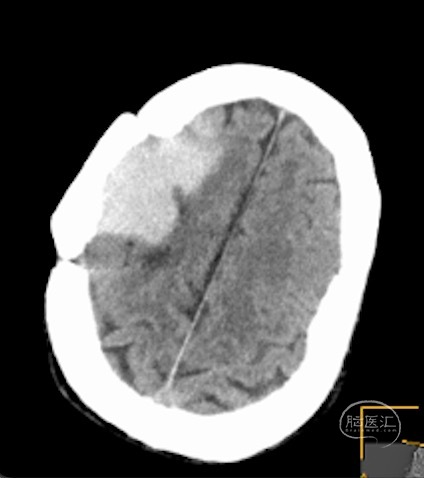

现病史:患者20余年前因蛛网膜囊肿手术后遗留伤口愈合不全,继发感染后治愈。随后多年来一直反复鼻腔流清亮液体,偶有发热,多发热后流液消失。近1个月无明显诱因下出现鼻腔流液,流出无色澄清液体,低头时鼻腔流液明显增多,每日有流液。无头痛不适,无恶心呕吐等症状。6小时前无明显诱因下突发头痛不适,无恶心呕吐,无意识障碍,无四肢活动受限。休息后头痛无明显好转,遂急诊送至我院,行头颅CT检查示右侧额叶出血。

额叶因低颅压出血!